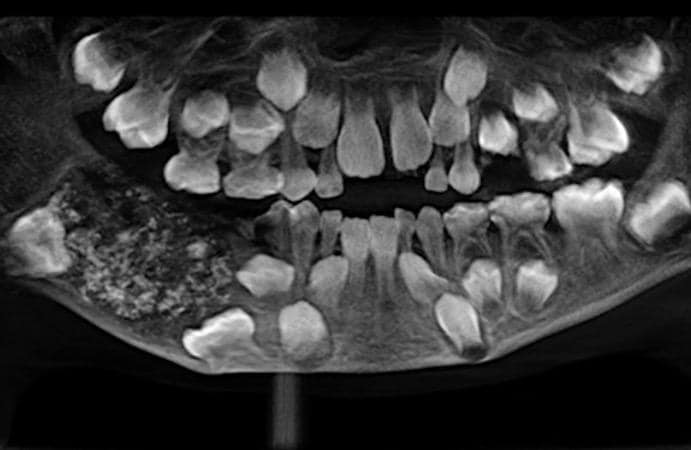

口内では、腫瘍のようなものが大きくなって永久臼歯の成長を妨げており、X線やCTスキャンで撮影すると、袋状の組織の中に複数の痕跡歯が写っていたことから、歯原生腫瘍のひとつ「複合性集合型歯牙腫」と診断された。これらの歯は口の外から見えないが、切除する必要がある。

2019年7月11日、歯の摘出手術が行われた。執刀医が重さ200グラムの腫瘍をひらき、0.1ミリ程度の極小サイズから1.5ミリの大きなものまで、様々な大きさの歯526本をすべて摘出。いずれの歯も歯冠と歯根があり、エナメル質で覆われていたという。